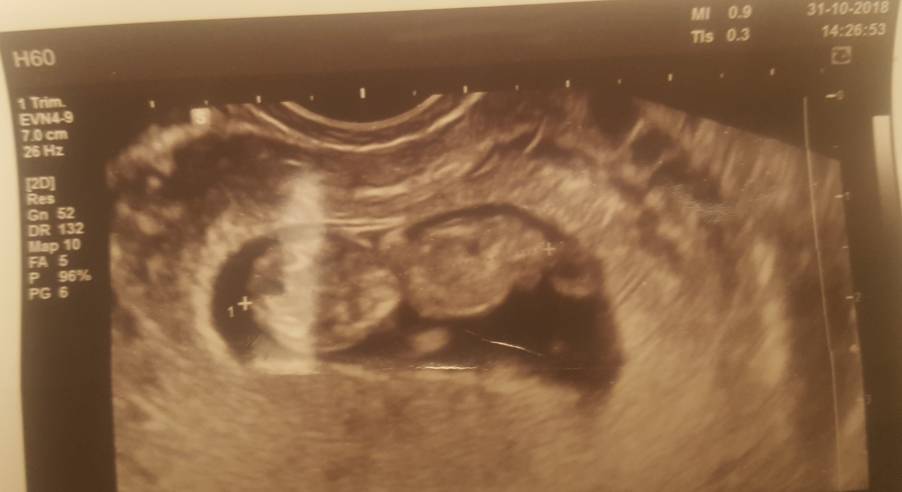

A to nasz wesoly ruchliwy maluszek, płci nie znamy ale to bez znaczenia wazne ze na usg wszystko w pozadku, wyniki pappa za tydz z tym ze lekaz juz mi zaznaczyl ze nie ma zlych wynikow i jakby co zeby nic sie nie martwic bo to tylko badania i jak cos bd robic wiecej.

Załączniki

• 20181031_232025.jpg

20181031_232025.jpg

1,1 MB · Wyświetleń: 131